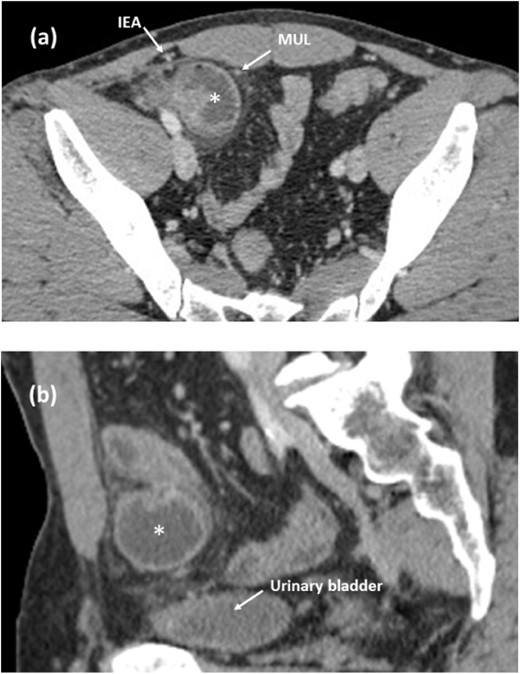

A 51-year-old man was presented with abdominal pain and vomiting. Contrast-enhanced computed tomography (CT) showed a dilated small intestine with a sac-like appearance in the right lower abdomen. The herniated small intestine was located between the MUL and the IEA (Fig. 1a) and did not compress the urinary bladder wall (Fig. 1b). The dilated inguinal canal was observed with extrusion of the extraperitoneal fat.

Contrast-enhanced CT images of the internal hernia in the medial inguinal fossa. (a, axial image) The herniated small intestine (asterisk) is located between the MUL and the IEA. (b, sagittal image) The herniated small intestine is apart from the urinary bladder. MUL, medial umbilical ligament. IEA, inferior epigastric artery.